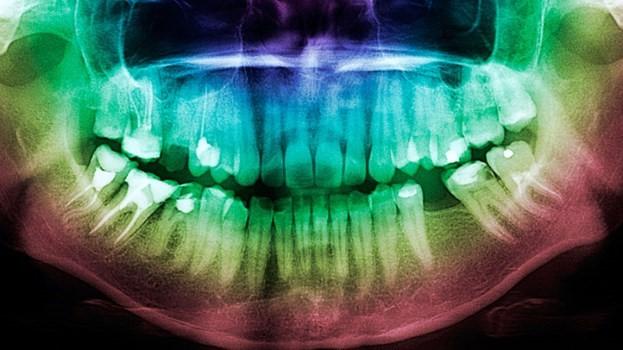

La pérdida de dientes es, sin duda alguna, otra gran desventaja que se presenta cuando se es diagnosticado con diabetes. Como ya sabemos, el cuidado dental a menudo es pasado por alto, conduciendo a una peor salud en general, sugiere el estudio.

El desgaste físico asociado con la diabetes tipo 2 incluye la pérdida de dientes, según lo encontrado en un estudio.

El riesgo de problemas de visión y amputaciones para personas con diabetes ya es bien conocido. Ahora, los estudios demuestran que los diabéticos pierden el doble de dientes en promedio que aquellos que no padecen esta enfermedad.

La enfermedad de las encías es una complicación común de la diabetes. Acerca de la mitad de los adultos en los Estados Unidos tienen enfermedad de las encías, y su prevalencia es incluso mayor entre los que padecen de diabetes, dice Wu.

“La última consecuencia de la enfermedad de las encías es la pérdida de dientes”, agrega ella.

La razón del por qué la diabetes está relacionada con la pérdida de dientes no ha sido aclarado, dice Wu. Lo que sí está claro es que la relación es bidireccional, explican los autores del estudio. Por un lado, la diabetes aumenta las probabilidades para una salud dental mala, mientras que los dientes y las encías en deterioro están relacionados a una peor salud en general en las personas con diabetes.